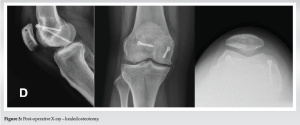

- X-ray (Fig. 1), computed tomography (Fig. 2) and magnetic resonance imaging showed Dejour type D trochlear dysplasia

- Anterior femoral bump visible in lateral view (9 mm)

- Radiographs showed complete bone healing and restored slope (Fig. 5).